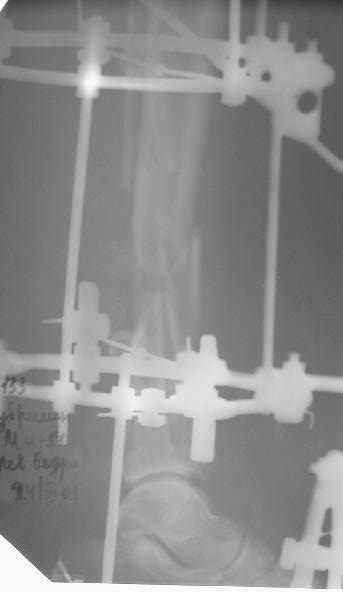

На дополнительных снимках итраоперационно видна значительная потеря массы (рис 6 рис 1). Хотя на снимках контрольных после операции вроде дефекта значительного нет. Все же придется, как-то замещать дефект костный на голени, думаю подготовить морально больного к повторной операции костной пластике, после заживления ран.